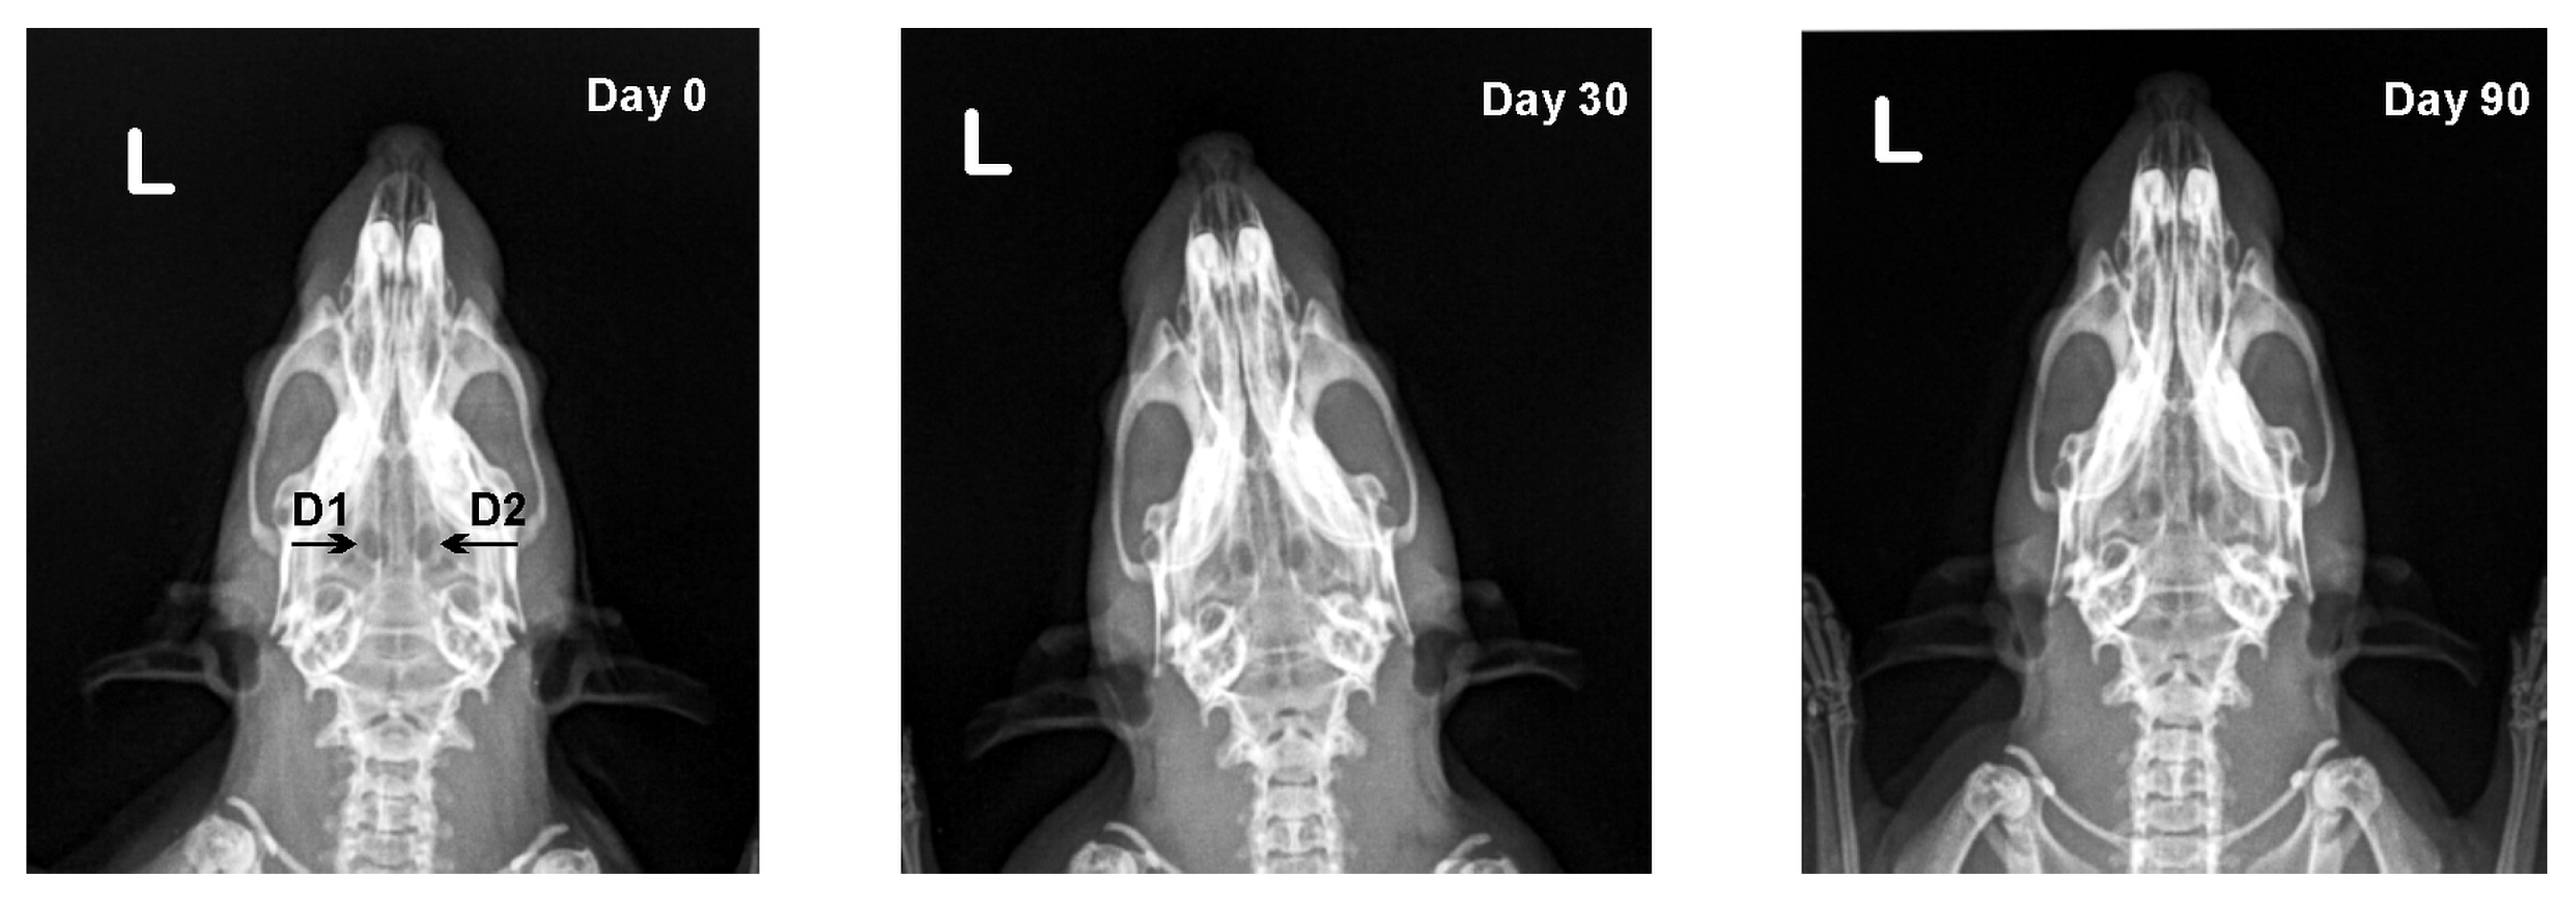

3.2. X-ray Results

| Defect | Day 0 | Day 30 | Day 90 |

|---|---|---|---|

| D1 | 0.92 ± 0.02 | 0.92 ± 0.03 | 0.93 ± 0.03 |

| D2 | 0.93 ± 0.02 | 0.93 ± 0.04 | 0.95 ± 0.04 |

| D3 | 0.92 ± 0.02 | 0.91 ± 0.03 | 0.90 ± 0.03 |

| D4 | 0.93 ± 0.01 | 0.92 ± 0.02 | 0.90 ± 0.02 * |

| D1 | 0 (0–0) | 1 (0–2) **# | 2 (1–2) ** |

| D2 | 0 (0–0) | 2 (2–3) *** | 2 (2–3) *** |

| D3 | 0 (0–0) | 0 (0–2) | 0 (0–2) |

| D4 | 0 (0–0) | 0 (0–2) | 1 (0–2) |